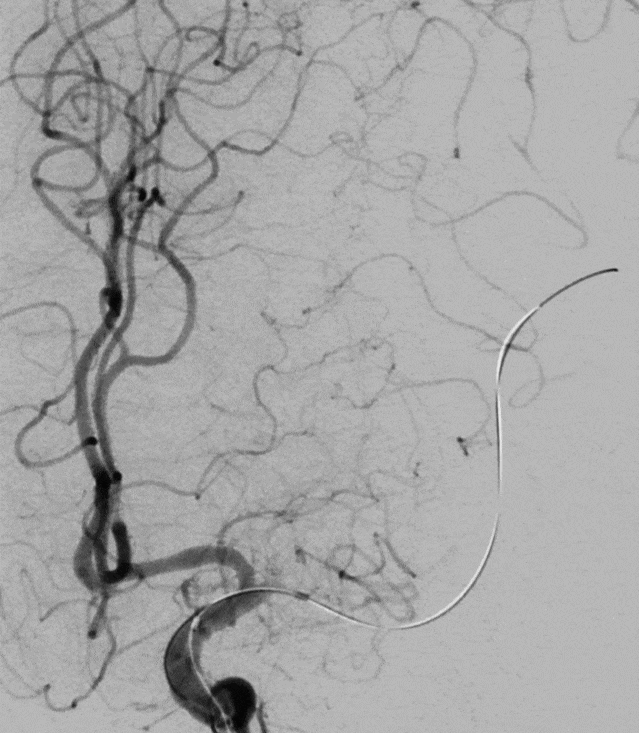

术前造影提示:左侧大脑中动脉闭塞,可见部分豆纹动脉显影,左侧大脑前动脉通过脑膜支代偿左侧大脑中上干。

中年男性患者,起病急,病情有进展加重表现,造影提示左侧大脑中动脉近端以远闭塞,大脑前部分代偿,造影闭塞为椎形征,考虑脑梗死发病机制为ICAS可能性大。拟行“BASIS技术”取栓及开通左侧大脑中动脉闭塞必要行支架植入术治疗。

0.014" 微导丝引导下支架微导管进入M2下干,保留导丝退回微导管,造影提示M2未见显影,考虑“首过效应”阴性。此时考虑病变性质狭窄基础上并大负荷血栓可能,不排除栓塞性病变可能。